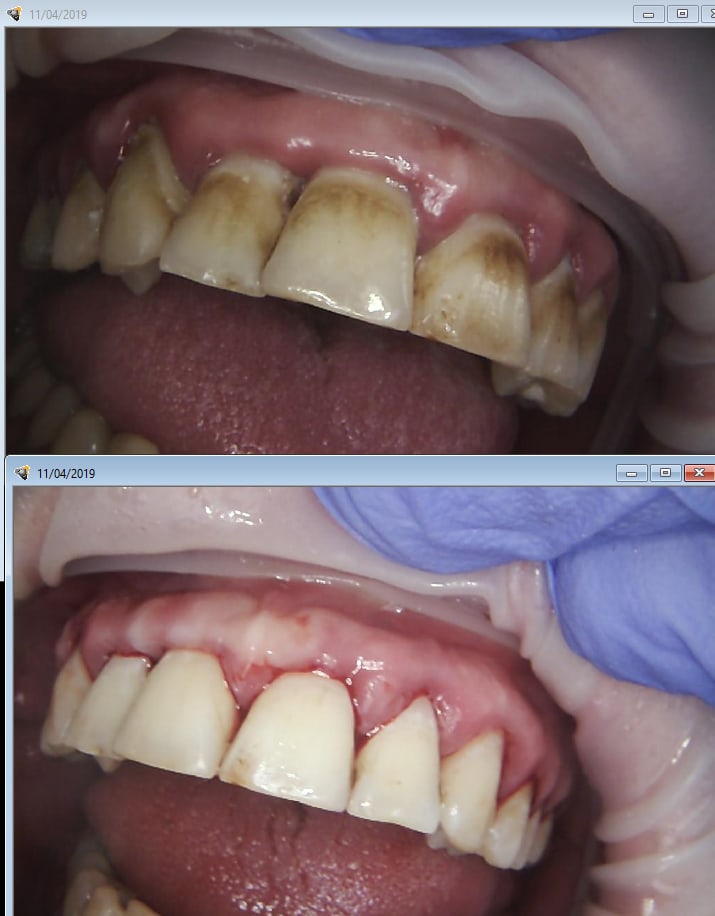

Detartrage cupules enhance uecfak - Eugenol